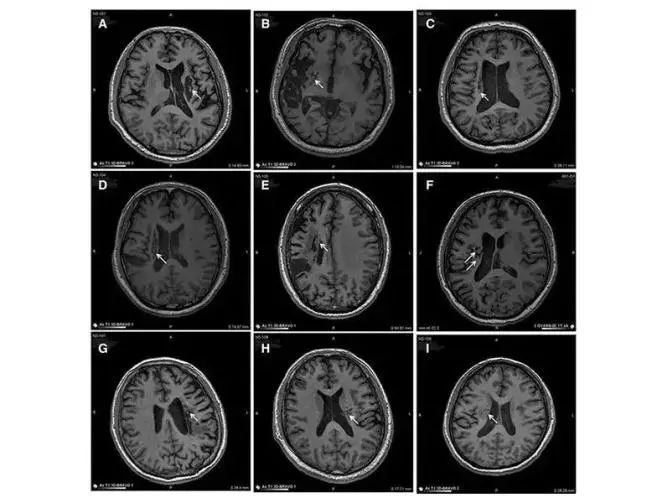

中風可導致神經元損傷。對干細胞轉運 MED 的研究表明,干細胞可以再生和修復受損的腦神經元,從而減少中風患者的后遺癥癥狀。在 9 名不同年齡的腦卒中偏癱患者中,將干細胞移植到腦梗塞區(qū)域取得了顯著的臨床效果。

9 名患者的成像顯示病變區(qū)域的組織發(fā)生了顯著變化。影像學顯示,移植到腦梗死病變中的干細胞分化為神經系統(tǒng)的各種細胞,分泌營養(yǎng)因子,促進神經和血管再生,修復受損的血腦液屏障,減少炎癥反應,促進腦梗死動物神經功能的恢復。結果,9 名臨床患者的偏癱癥狀明顯改善。